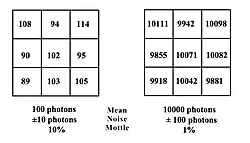

Let’s continue by considering two equally-sized small areas of a hypothetical digital image containing nine pixels. And let’s consider that the number of X-ray photons collected by each pixel is given by the numbers in Figure 6.16. We can estimate that for the area on the left, the average number of photons detected is 100, while that on the right, possibly as a result of lower attenuation, collects an average of 10,000 photons. The variation in the individual pixels within each area can be estimated statistically from the standard deviation of the number of detected photons. The standard deviation can be calculated from the square root of the mean when the photon number is assumed to follow a Poisson distribution as is the situation in radiography. The variation arises because of the random nature of X-ray emission that occurs within the anode of the X-ray tube and gives rise to what is called Quantum Noise.

Quantum noise is generally expressed as being plus/minus one standard deviation of the mean. The noise in our panel on the left is therefore ±10 photons, while that on the right is considerably higher at ±100 photons. It can therefore be inferred that noise increases with the number of X-rays detected. On this basis, it can be concluded that noise increases with radiation exposure, i.e. mAs.

The mottle is given by the ratio of the noise to the mean number of photons and therefore is 10% for the left panel and just 1% for that on the right. The mottle as a result is more apparent in the left than it is in the right. In other words, mottle decreases with increasing radiation exposure so that subtle contrasts become more conspicuous.

The Signal-to-Noise Ratio (SNR) is a more general concept applied in this form of image analysis and is given by the ratio of the noise to the mean signal. Therefore, its 10:1 on the left, while its considerably higher at 100:1 for the right hand panel. We can infer therefore that the SNR increases with increasing radiation exposure, implying improved image quality at higher mAs and for lower attenuating tissues.